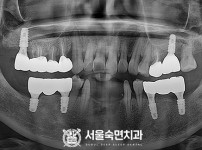

임플란트-전후사진3

치과를-선택할-때-꼭-확인하세요-서울숙면치과-임플란트-전후사진